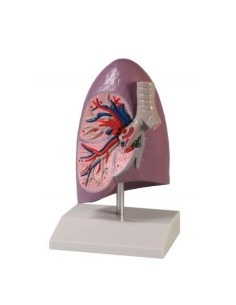

Dal cranio in 22 parti con incastri magnetici ai modelli di colonna vertebrale, da quelli di articolazioni a quelli di cuore, ogni pezzo della nostra collezione è progettato per un’immersione totale nello studio dell’anatomia umana. I nostri modelli, realizzati tramite scansioni di ossa vere, garantiscono un’esperienza tattile autentica e una fedeltà di peso quasi identica agli originali.

Essenziali per studenti e professionisti, i nostri modelli anatomici sono strumenti didattici che permettono di osservare le strutture anatomiche con precisione, eliminando la necessità di dissezioni o studi invasivi. Sono inoltre utili per spiegare ai pazienti le patologie, rendendo la comunicazione più efficace e risparmiando tempo prezioso.